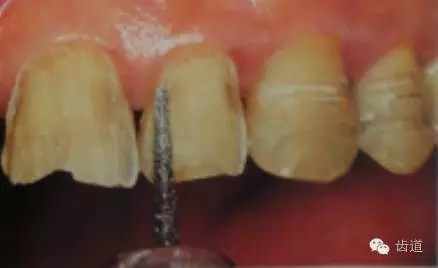

1、唇面預備:先用定深車針定出定深溝,再換合適車針磨除剩余的釉質。

唇面磨除的量依據所用貼面材料及牙齒的變色程度而定。

如下圖: